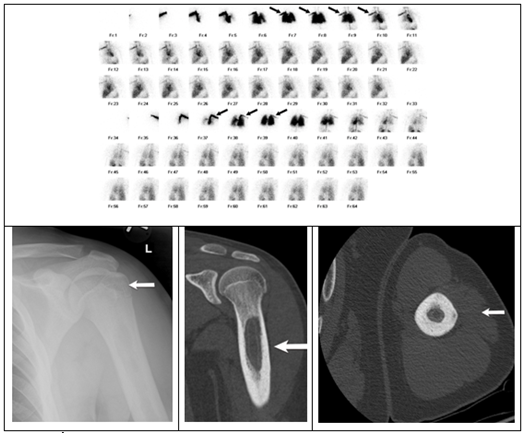

3. Figure 3C: 3 phase bone scan demonstrating increased radiotracer activity in the proximal to mid-hummers.

Figure 4 Patient 4 imaging review.

Figure 3 Patient 3 imaging review.

1. Figure 3A: AP view X-ray of the left hummers showing cortical sclerosis.

2. Figure 3B: Coronal and axial CT scans showing cortical sclerosis with intramedullary calcifications consistent with long staging sclerotic reparative lesion with both endosteal and periosteal components.